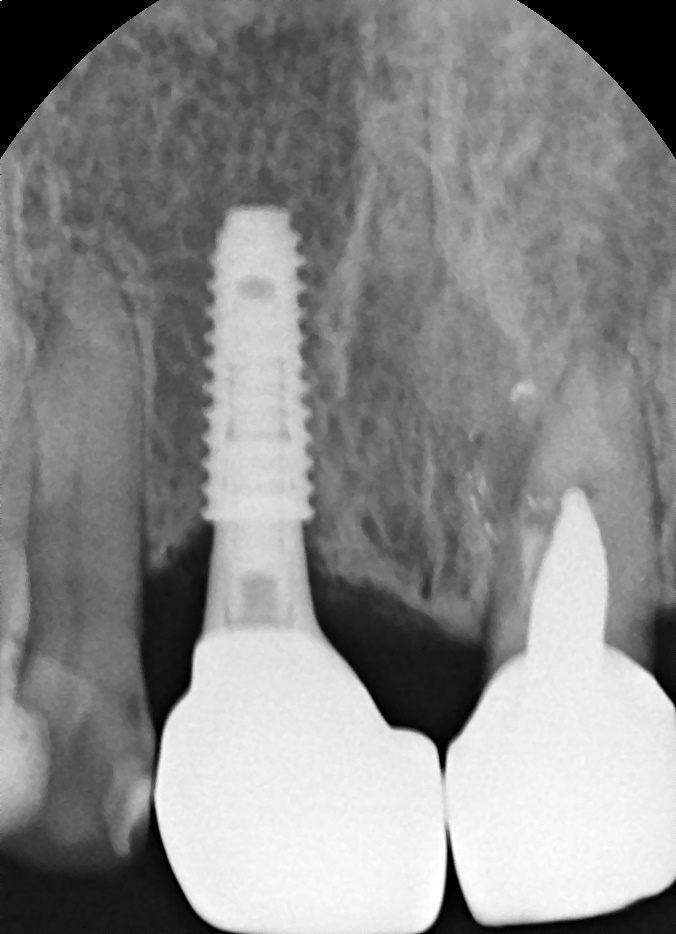

일단 엑스레이를 촬영해보니 다행히도 임플란트 픽스처는 깨지지 않은 것으로 확인되었고,

픽스처가 뼈와 잘 유착되어 있는지 수치로 체크한 결과 이상이 없어서 1~2주 정도 지켜본 후

어버트먼트와 크라운만 다시 제작해 붙여드렸습니다.

만약 이 픽스처가 깨졌다면 어떻게 되었을까요?

픽스처가 깨지거나 금이 갔다면 이 픽스처를 제거하고 다시 식립해야 할 가능성이 매우 높습니다.

즉, 깨진 픽스처를 완전히 제거하고 재수술을 해야하는 것이죠.

잇몸뼈에 단단하게 붙어 고정되어 있는 인공치근을 제거하고 다시 식립하는 것은 처음 식립할 때보다 더 까다롭고 어렵습니다.

따라서 풍부한 임플란트 수술 및 재수술 경험을 갖춘 전문의에게 수술받으시는 것을 권장해 드립니다.